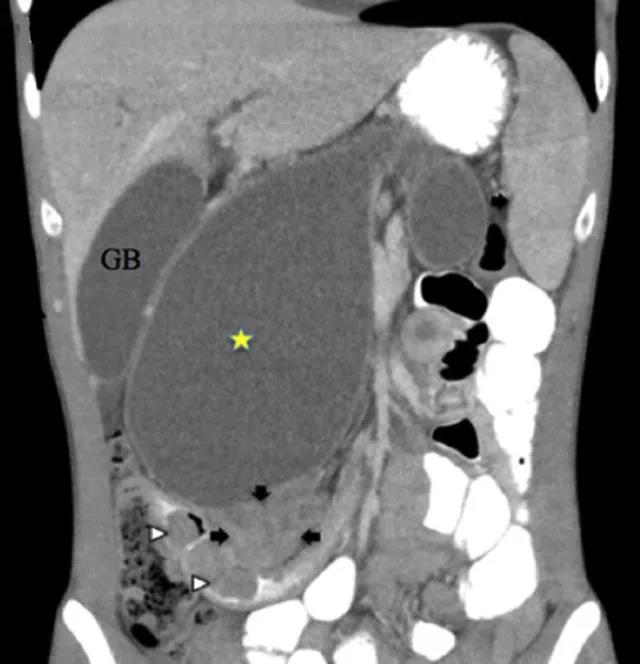

腹部 CT 结果显示: 右腹部见一充满液体的囊性结构(图 2)。

图 2  CT 显示右腹部有一液性包块(黄色星号),可见壶腹部肿物(黑色箭头)侵犯十二指肠(白色箭头)。注释:GB,胆囊

事实上,该囊性结构其实为扩张的胰管。因壶腹部肿物侵犯了十二指肠,导致继发性胰管扩张。

患者行超声内镜检查后证实,十二指肠腔中有一来源于壶腹的 4 cm 肿物。